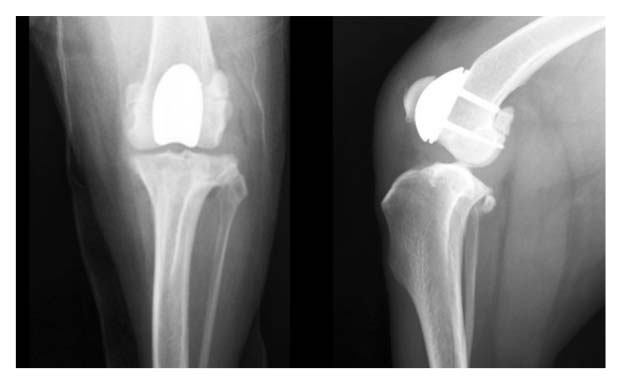

Due to the severe grade 4 right LPL, radiographs were made to assess for an underlying angular limb deformity, which was confirmed.

Further radiographs were not pursued due to the multiplanar (frontal, sagittal, and transverse) limb deformities, as deformities of this significant nature cannot be accurately assessed radiographically using a traditional segmental technique.

Radiographs:

Osteotomies healed with stable implants, reduced patella, and joint alignment

Restored right stifle full range of motion and pain-free weight bearing on her right pelvic limb

Resolved grade 4 lateral patella luxation and angular limb deformities